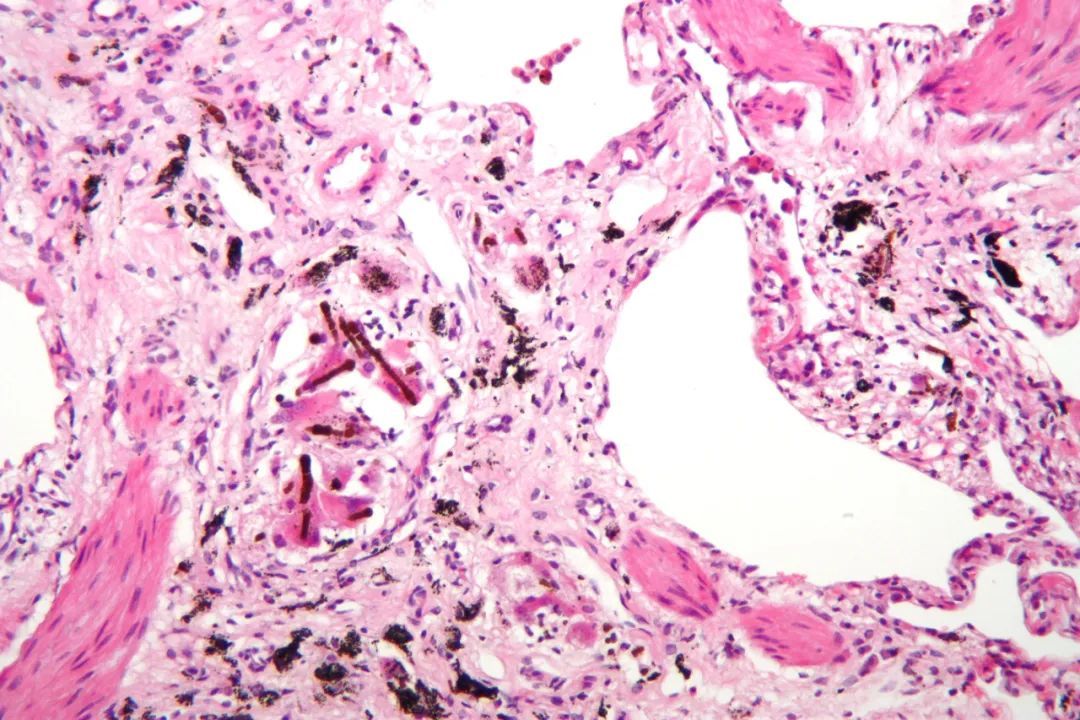

硅肺病患者肺部组织染色后的图像,黑色颗粒是杂质

当大量的沙尘被吸入人体时,它们会嵌入肺部的微小泡囊中,然后被肺内的巨噬细胞所吞噬。但沙尘不能被巨噬细胞所自行分解,导致巨噬细胞死亡,释放所吞噬的粉尘,然后恶性循环,造成更多细胞受损,造成肺机能的障碍。这是一种治不了的病,只能通过洗肺来缓和症状,延长一下寿命。